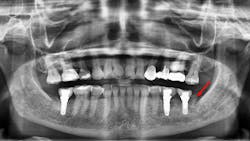

Failures and complications associated with bone augmentation can have a devastating effect on the outcome of dental implant treatment. These complications are classified as either early or late. Early complications include wound dehiscence, membrane and graft exposure, and infection, with the most common complication being wound dehiscence (figures 1a–1c). A strong correlation has been shown between flap tension and wound dehiscence, with wound breakdown occurring in 40% of cases where the flap tension reached 40.1 N as opposed to 10% for flap tensions < 0.1 N.1

Figures 1a–1c: Wound dehiscence occurring after bone augmentation procedures.